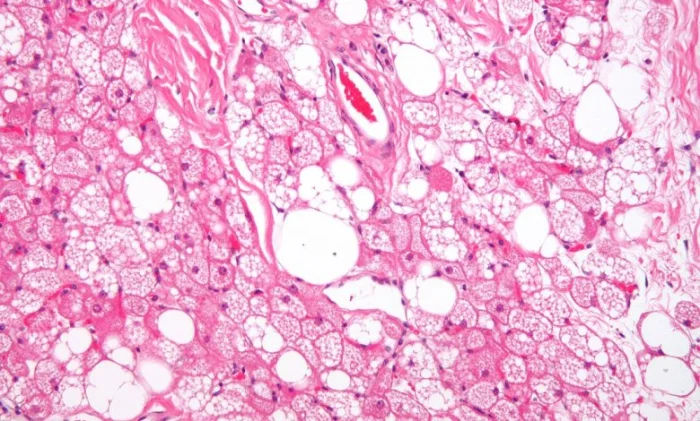

Исследователи из Шанхайского университета Цзяо Тун и Шанхайского института пластической и реконструктивной хирургии продемонстрировали, что обработанная особым образом жировая ткань способна самоорганизовываться в структуры, напоминающие костный мозг, панкреатические островки и даже нервную ткань. Ключевым элементом метода является использование так называемого реагрегированного микрожира – небольших пеллет, сохраняющих естественное клеточное разнообразие и микроокружение ткани. При культивировании в суспензии эти фрагменты самостоятельно реорганизуются и дифференцируются.

В эксперименте ученым удалось получить органоиды, представляющие все три зародышевых листка. Наиболее впечатляющие результаты были достигнуты при создании «очеловеченных» органоидов костного мозга. После имплантации мышам с иммунодефицитом пеллеты сформировали костные структуры с сосудистыми и эндостальными нишами, способные поддерживать человеческий гемопоэз – кроветворные стволовые клетки успешно приживались, размножались и дифференцировались.